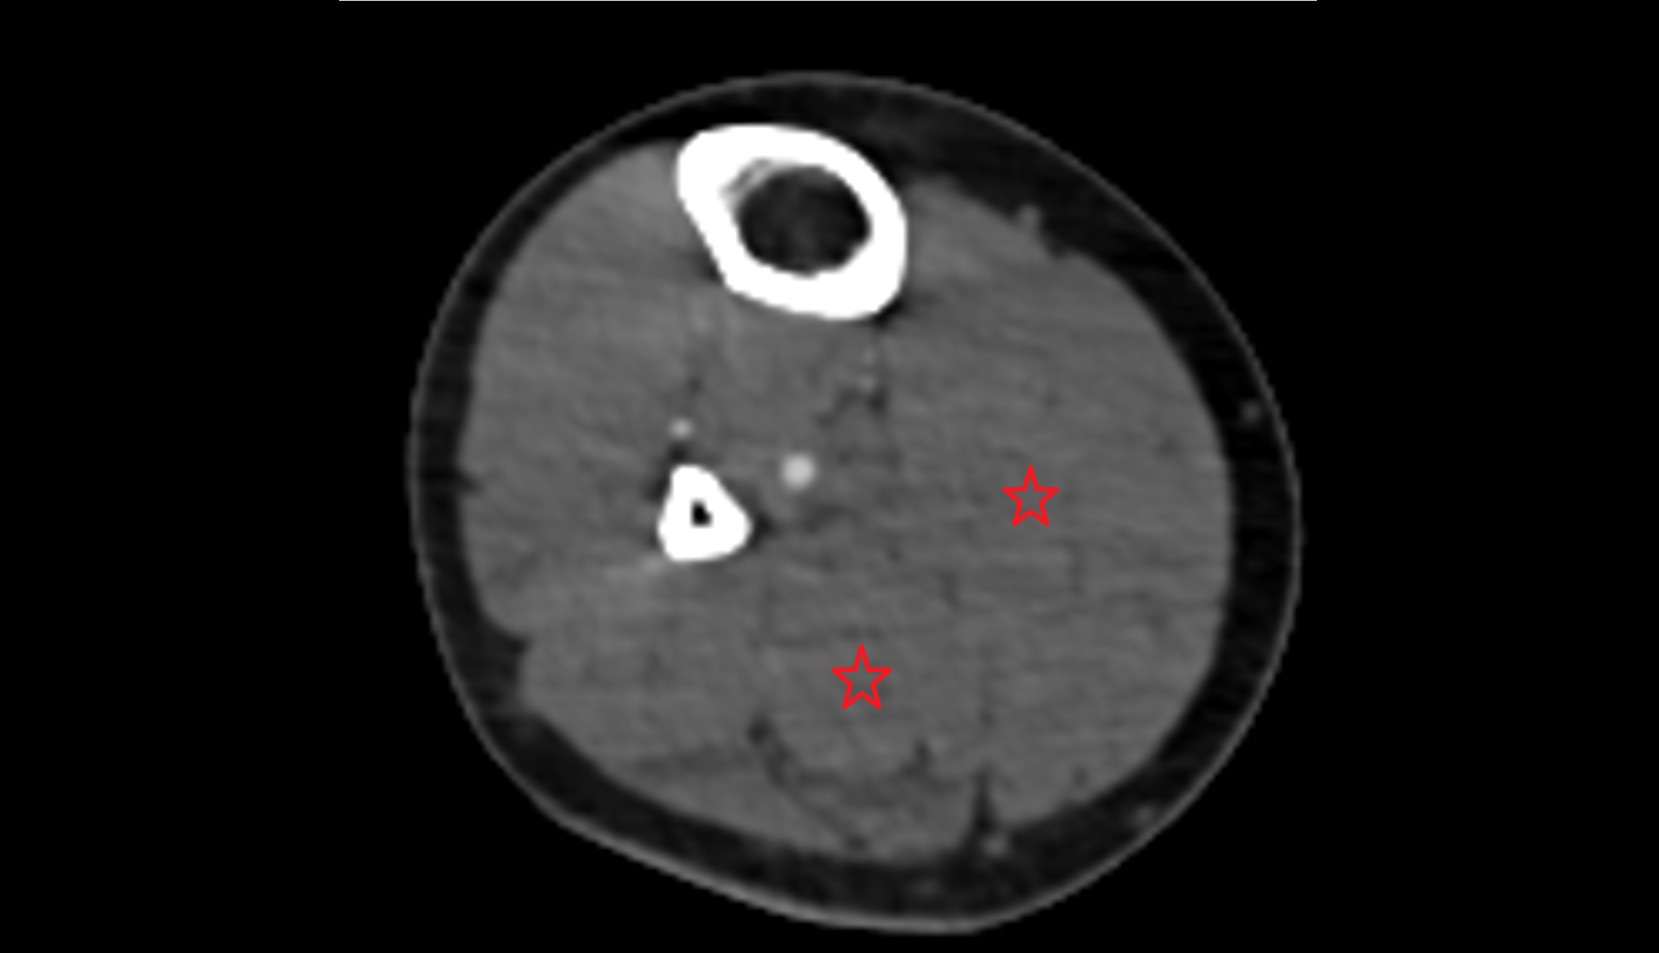

- Popliteal artery

- Popliteal vein

- Common fibular nerve

- Tibial nerve